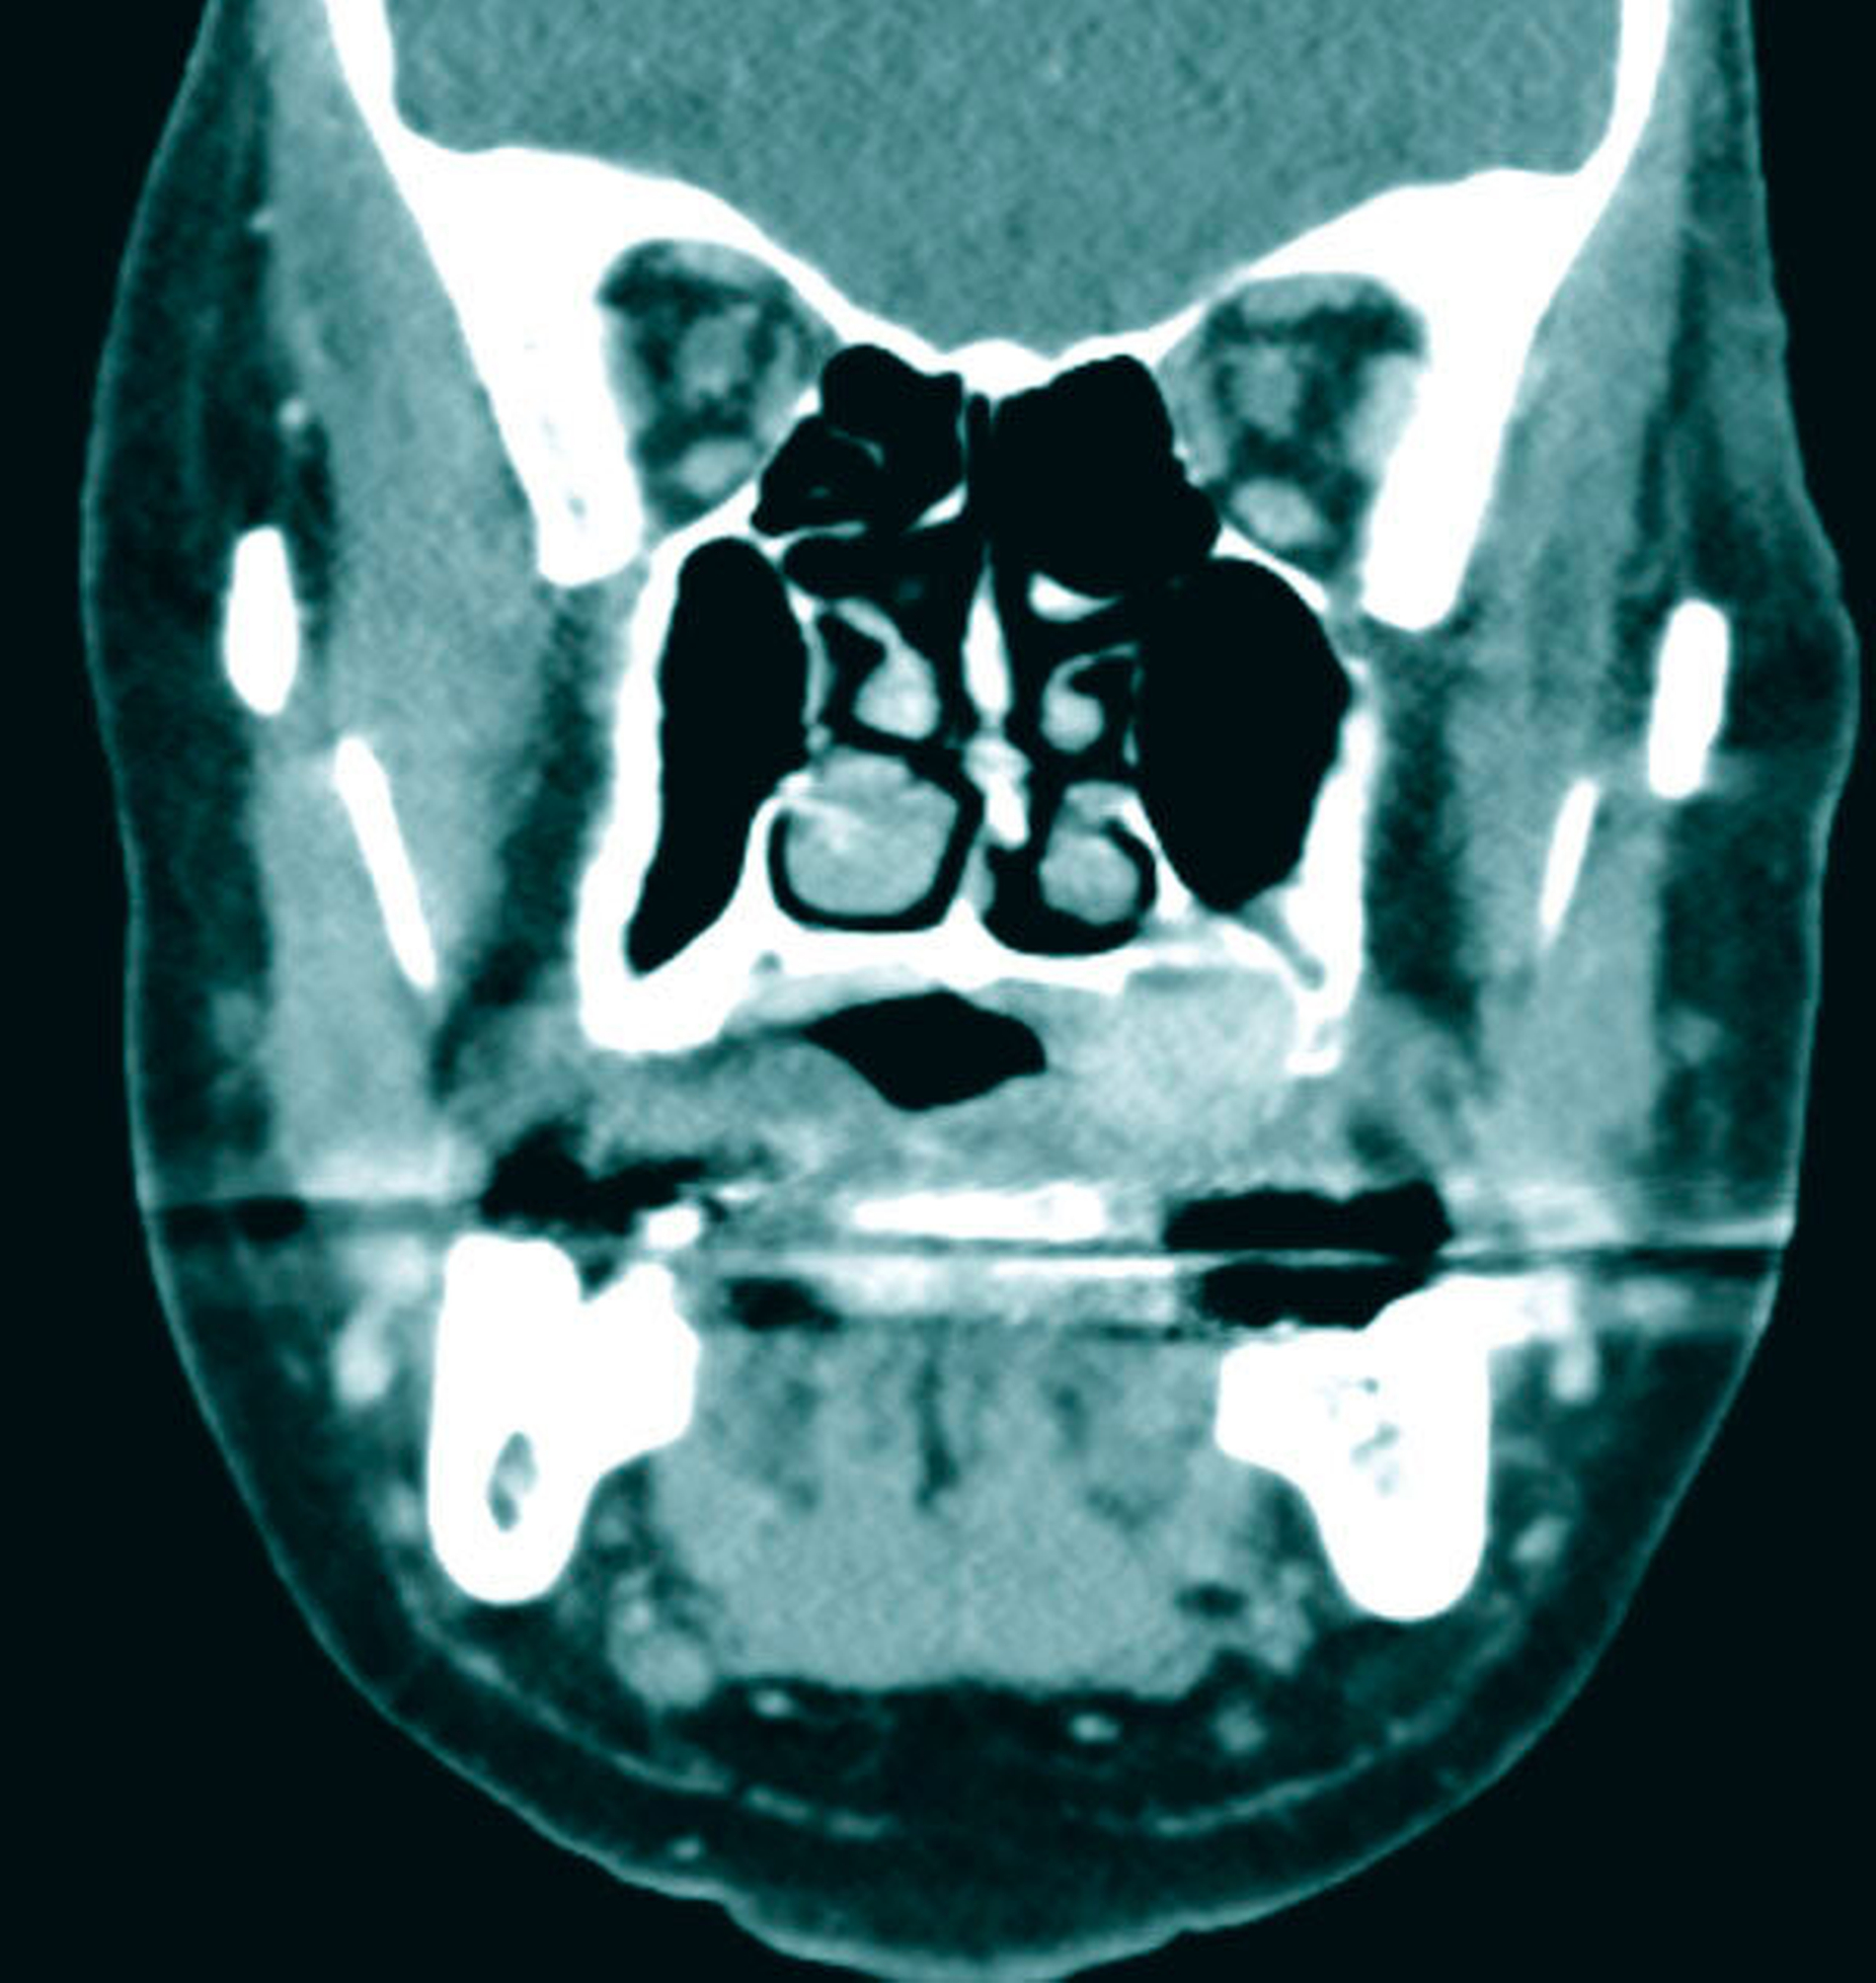

Zum Zeitpunkt der Untersuchung zeigte sich im linken Oberkiefer palatinal regio 26/27 ein livider braun-rötlicher Tumor von etwa zwei Zentimeter Größe mit Verdrängung der fixierten Gingiva nach krestal. Nach palatinal-medial war das Bindegewebe unter reizloser Schleimhaut aufgetrieben (Abbildung 1). In der Bildgebung mittels Panoramaschichtaufnahme zeigte sich in der interessierenden Region eine Verschattung der linken basalen Kieferhöhle mit Auflösung des krestalen Knochens im Molarenbereich. Des Weiteren war ein retinierter Zahn 48 und ein horizontal-vertikaler Knochenabbau bei bekannter Parodontitis zu erkennen (Abbildung 2). Zur weiteren Diagnostik wurde eine Computertomografie des Kopfes und bei Verdacht auf mögliche Metastasierung der vorbekannten Malignome eine Computertomografie des Thorax und Abdomens durchgeführt. Hierbei zeigte sich die bereits diagnostizierte Raumforderung im Bereich der linken basalen Kieferhöhle mit partieller Auflösung des molarennahen Knochens und einer weichteildichten Raumforderung im Bereich der basalen Kieferhöhle. Die kranialen Anteile der Kieferhöhle waren belüftet (Abbildung 3). Ein Anhalt für eine Metastasierung oder ein Rezidiv des Urothel- bzw. Prostatakarzinoms bestand nicht. In dem durch eine Inzisionsbiopsie in Lokalanästhesie entnommenem Gewebe zeigte sich histologisch eine teils glandulär, teils kribriform konfigurierte epitheliale Proliferation mit teils basophilem Stroma. Es lag eine deutliche Positivität für CK7 und S100 ohne Färbereaktion für CK5/6 vor. Somit entsprach der Befund dem eines kanalikulären Adenoms. Der Tumor wurde in Intubationsnarkose entfernt. Zur Kieferhöhle bestand eine dünne knöcherne Abgrenzung, die belassen wurde. Eine endoskopische Untersuchung über den mittleren Nasengang zeigte bis auf zwei kleinen Schleimretentionszysten oberhalb der Läsion – die jeweils entfernt wurden – keine weiteren Auffälligkeiten. Der Defekt wurde durch eine Einlagerung des Bichat’schen Fettkörpers und eines Mukoperiost-Lappens von vestibulär gedeckt. Die finale histologische Beurteilung bestätigte die Diagnose und eine vollständige Entfernung. Nach einem unkomplizierten postoperativen Heilungsverlauf zeigte der Patient in der klinischen Nachsorge nunmehr sechs Monate nach Operation keinen Anhalt für ein Rezidiv.

Zur Diagnostik kann entweder eine Magnetresonanztomografie oder bei knöcherner Beteiligung eine Computertomografie durchgeführt werden. Bei reinen Weichgewebstumoren der Oberlippe oder Wange kann auch eine Sonografie ausreichend sein. Das radiologische Bild entspricht einer gut abgrenzbaren Weichteilmasse mit mitunter lokal aggressivem Wachstum und knöcherner Destruktion [Smullin et al., 2004].